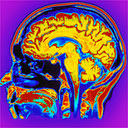

Il crimine può essere prevenuto. Prima che accada, quando è ancora solo nella mente del potenziale autore. Era la promessa della Precrime, l’unità di prevenzione del crimine di Minority Report, il romanzo di fantascienza di Philip Dick, poi fortunato film con Tom Cruise. Ma ora i ricercatori del Max Planck Institute for Human Cognitive and Brain Sciences di Monaco di Baviera assicurano: siamo riusciti a leggere nel cervello le intenzioni prima ancora che si trasformino in azioni, grazie a sofisticati algoritmi sui dati di una risonanza magnetica sull’attività cerebrale.

"E’ stato come accendere una torcia nel buio e agitarla alla ricerca di una scritta su di un muro", spiegano gli scienziati, che hanno previsto con il 70% di successo cosa avrebbero deciso di fare dei volontari che potevano scegliere se sommare o sottrarre due numeri apparsi su uno schermo. “La regione cerebrale dove si concentrano le intenzioni è la superficie della regione prefrontale della corteccia, dove i programmi vengono immagazzinati come in un deposito, prima che si decida di tradurli in vere e proprie azioni".